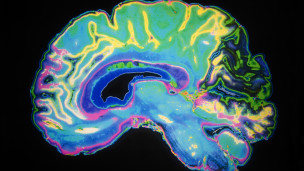

¿Podemos «leer» las ideas políticas en un escáner?

¿Podemos «leer» las ideas políticas en un escáner?

La política es una de las áreas más complejas del pensamiento humano. Así que fui escéptica cuando oí que escanear el cerebro de una persona podría predecir sus elecciones políticas.

La ciencia cognitiva está logrando avances extraordinarios, pero mapear las interacciones sociales humanas con lo que se puede medir en un escáner del cerebro es un salto enorme.

Pero en Estados Unidos y en Reino Unido, psicólogos y neurólogos están haciendo serias investigaciones para intentar relacionar las actitudes políticas con lo que está dentro de nuestro cráneo.

«Al observar cómo el cerebro está procesando los fenómenos políticos, podemos comprender un poco mejor por qué hacemos lo que hacemos», dice Darren Schreiber, de la Universidad de Exeter, en Reino Unido.

Schreiber comenzó usando la técnica de imagen por resonancia magnética (IRM) para investigar patrones de actividad en el cerebro cuando las personas tomaban decisiones, especialmente aquellas que involucraban riesgos.

Varias investigaciones buscan la relación entre patrones de actividad del cerebro y las ideas políticas.

Varias investigaciones buscan la relación entre patrones de actividad del cerebro y las ideas políticas.

Mientras que las decisiones no eran todas tan diferentes, el experto vio variaciones en las partes del cerebro que eran más activas en las personas que se describían a sí mismas como conservadoras y en aquellas que se consideraban liberales.

El científico no generaliza sobre cómo piensan exactamente conservadores y liberales, pero cree que su trabajo sugiere que diferentes actitudes políticas reflejan divergencias profundamente enraizadas en cómo entendemos el mundo.